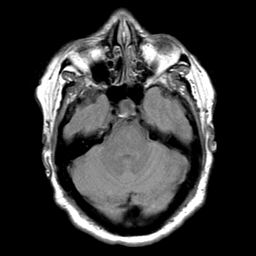

Cerebral hemorrhage, MR Study mr-pd -- Slice #7

[Home][Help][Clinical] Slice 7